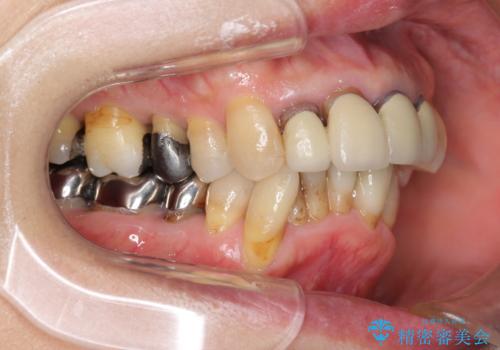

- 上顎前歯の黒ずみの改善、下顎前歯の十度なガタつき、矯正治療とセラミック治療を含む全体的な治療を希望され来院されました。

銀歯を高強度の仮歯に替えたのち、下顎前歯のみの部分矯正→全体的なマウスピース矯正治療(インビザライン)→最終的なセラミック治療と治療を進めます。

矯正治療と目立つ銀歯のやりかえを行ったことでかみあわせだけでなく、審美性・清掃性も改善し口腔内の環境を劇的に改善することができました。